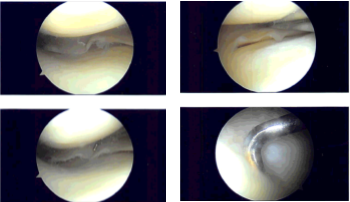

Medial anterior portal was made with the use of a spinal needle and knife. Examination of the medial femoral compartment showed horizontal and oblique tear of the lateral free margin along the body of the posterior hom. This was done with the use of straight biters and shavers.

Balanced margins could be achieved. Examination of the rest of the tibiofemoral compartment was good. Examination of the infrapatellar notch showed an intact ACL. Examination of the lateral tibial compartment showed intact meniscus.

There was Grade III medial injury to the articular cartilage which was debrided to balanced margins. The bone was then exposed. Examination of the patellofemoral compartment showed intact cartilage. Final pictures were taken and saved.

Intraoperative Arthroscopy Images